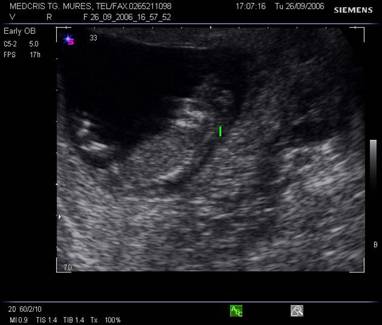

Fig. nr.112 Sarcina 12 saptamani la ecografia transvaginala